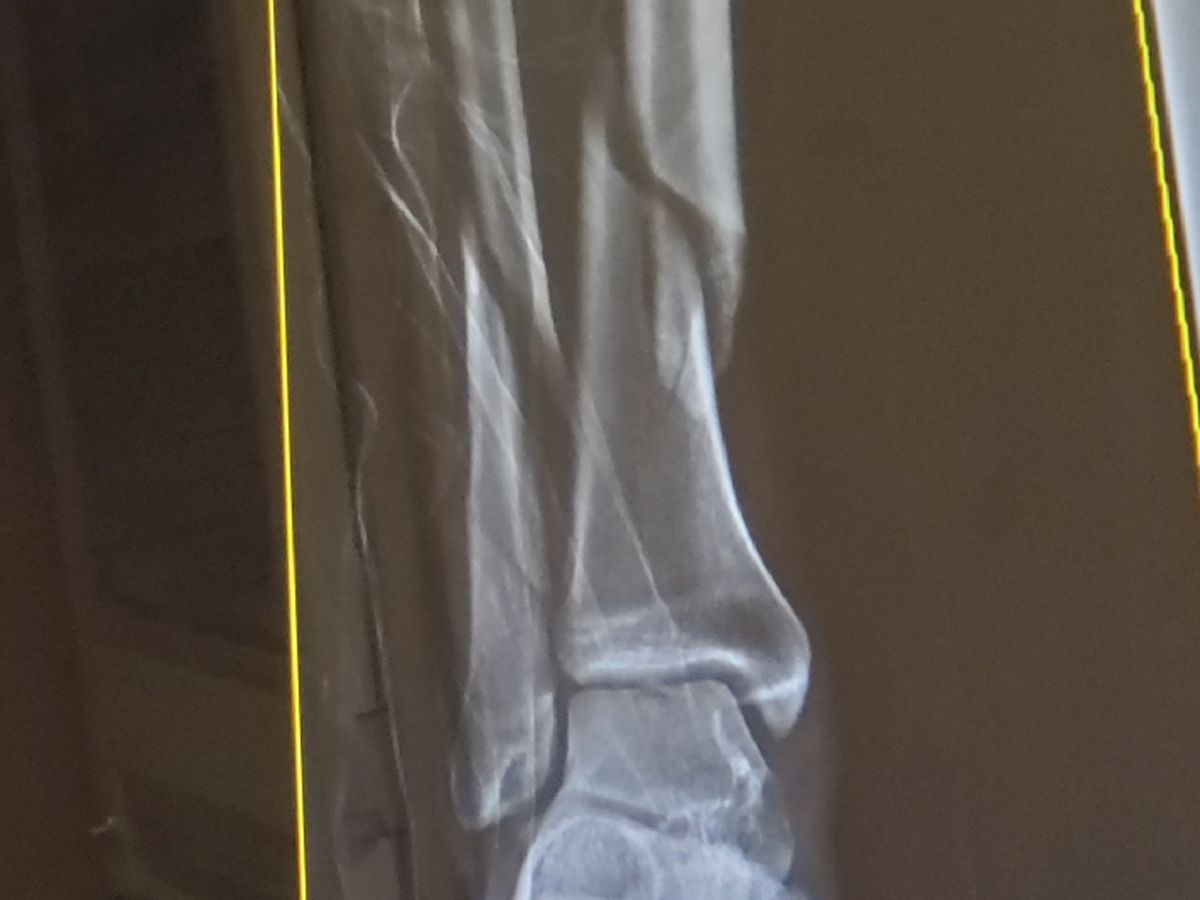

Hello I am Scott Blackman. As many of you may or may not know, 2019 was a rough year for me. I suffered a variety of setbacks both legally, financially and physically. Recently just before the holidays i suffered a severe break in my right leg. It was a break that affected both my tibia (shin bone), and the fibula snapping them both in two. I had a very successful surgery and have been recovering very well. As many of you have experienced before I am sure, however with limited compensation from insurance, and the high cost of medical procedures in general added to time missed from work I have fallen way behind on my normal bills. I have recently returned to work, but it will be awhile before I will be back to normal birth physically and financially. I am behind on my rent, have maxed out credit cards and borrowed from my company all to try and keep me afloat. My personal responsibility after insurance for surgery and ambulance e.t.c already is right around $6,000 and I expect there will be more fees trickling in. Gaining partial disability pay from my insurance company is very little and is a long drawn out process that will not help much. It is with great humbleness that I reach out to you and ask for assistance. The holidays are always brutal on people's pocketbooks which I am totally aware, so the timing couldn't be worse, but I am truly humbled and thankful for whatever you may be able to contribute. Thank you!!